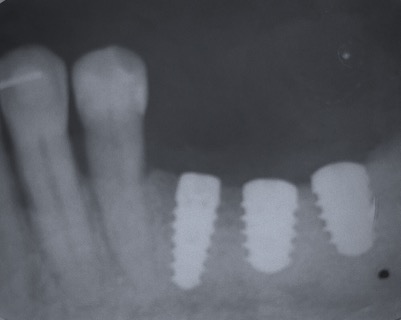

Un impianto dentale o fixture è un corpo in titanio, totalmente biocompatibile, che viene posizionato nella mascella o mandibola con lo scopo di sostituire la radice di un dente naturale perso. Su di esso viene successivamente o immediatamente quando possibile (carico immediato) fissata la protesi ovvero la corona del dente restituendo funzione ed estetica.

Gli impianti non hanno scadenza quindi non sono un rimedio temporaneo ma una soluzione definitiva per tornare ad avere denti come quelli originali. L’osteointegrazione è così forte e perfetta che se volessimo rimuovere l’impianto in un secondo momento dovremmo togliere anche l’osso che lo circonda.

Con l’implantologia oggi è possibile sostituire un solo dente come un’intera arcata anche in casi di deficit ossei grazie alla GBR (rigenerazione ossea guidata) che ci permette di intervenire quando la disponibilità ossea iniziale del paziente non sarebbe sufficiente.